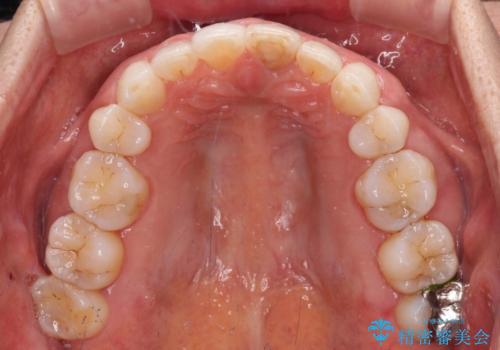

矯正治療の後戻り インビザライン・ライトでの再矯正

- 上下前歯を中心に、以前行った矯正治療の後戻りが気になるとのことで来院された患者様です。

後戻りは軽度であったため、インビザライン・ライトにて治療を行うこととしました。

矯正治療後は、再度後戻りすることを極力回避するために、下顎前歯の舌側を細いワイヤーを用いて保定することとしました。